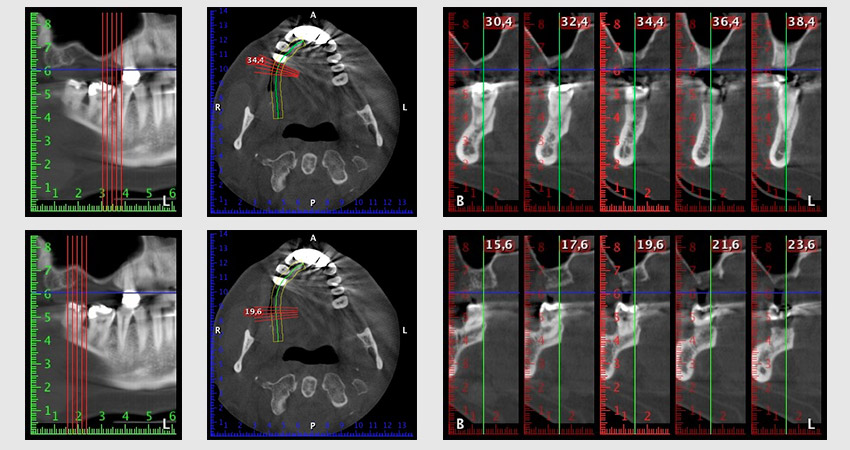

Unos seis meses después de la extracción de las piezas 16 y 14 se realizó una tomografía digital de volúmenes (DVT, Planmeca) para realizar una planificación adecuada y reducir los riesgos al mínimo. En este punto se constató que el hueso no se había regenerado en la cantidad deseada (figuras 2 a 7).